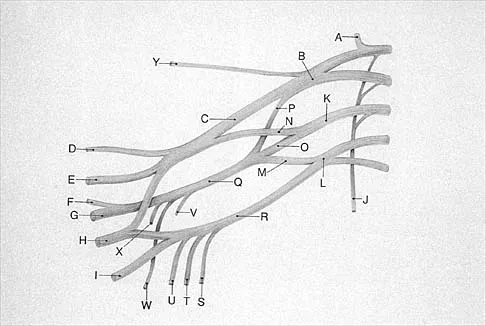

Question 86

What structure is marked Q in the diagram of the brachial plexus shown in Figure 22?

Explanation